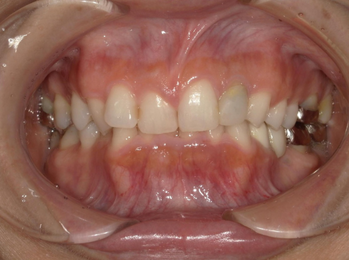

After Photo

After

主訴

ガタガタ、八重歯が気になる。

治療期間

2年5か月

料金

相談料0円、検査料33,000円、動的矯正治療費990,000円、保定装置料5,500円x5枚(必要枚数)

治療概要

歯が並ぶ隙間が足りないため、歯列を拡大して隙間を確保し、ガタガタと八重歯を改善しました。

過蓋咬合の改善は上下前歯を垂直的に移動させた。

矯正での歯の移動のリスクとして歯根吸収、歯肉退縮、歯髄怪死が考えられます。

保定装置の装置を怠ると隙間が生じてくる可能性があります。